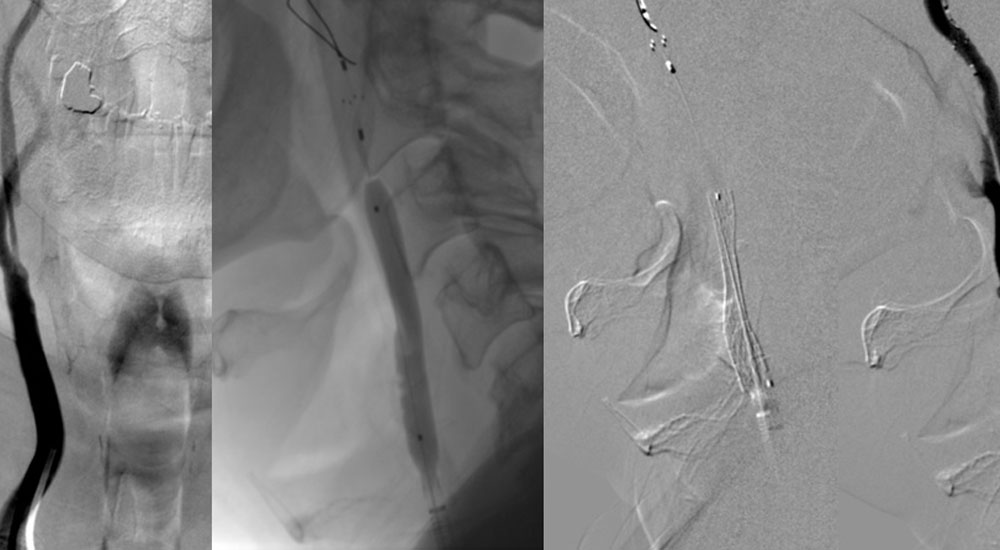

Digital subtraction angiography (DSA) is a fluoroscopic technique used extensively in interventional radiology for visualizing blood vessels. Radiopaque structures such as bones are eliminated ("subtracted") digitally from the image, thus allowing for an accurate depiction of the blood vessels.

Digital subtraction angiography, whereby a pre-contrast image is acquired, then subtracted from subsequent post-contrast images, was made possible in the 1970s, thanks to real-time refreshing of the resulting images.